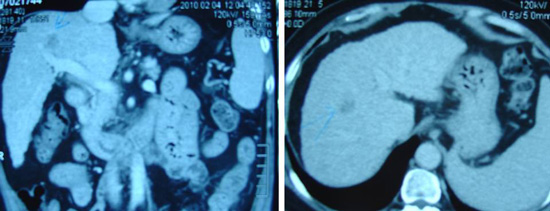

Tidak puas, PC lalu pergi ke sebuah rumah sakit swasta di Ipoh. Pada pemeriksaan X – ray didada kirinya menunjukkan adanya efusi pleura (yaitu adanya cairan di paru-paru kirinya). Cairannya disedot keluar. Sebuah ultrasonagraphy ( dibagian perut ) pada tanggal 23 September 2009 menunjukkan sebuah lesi berukuran 2,6 cm ( diperkirakan hepatoma atau kanker hati) di lobus sebelah kanan. Selain itu, pada organ hatinya sudah terjadi sirosis hati ( mengeras ) dengan hipertensi portal dan adanya ascites ( adanya cairan dibagian perut ). Organ Limpa nya membesar.

Biopsi dari lesi tersebut tidak dapat dilakukan mengingat telah terjadinya ascites, trombosit yang rendah dan keberadaan tumor yang terlalu dalam dan berdekatan dengan vena portal.